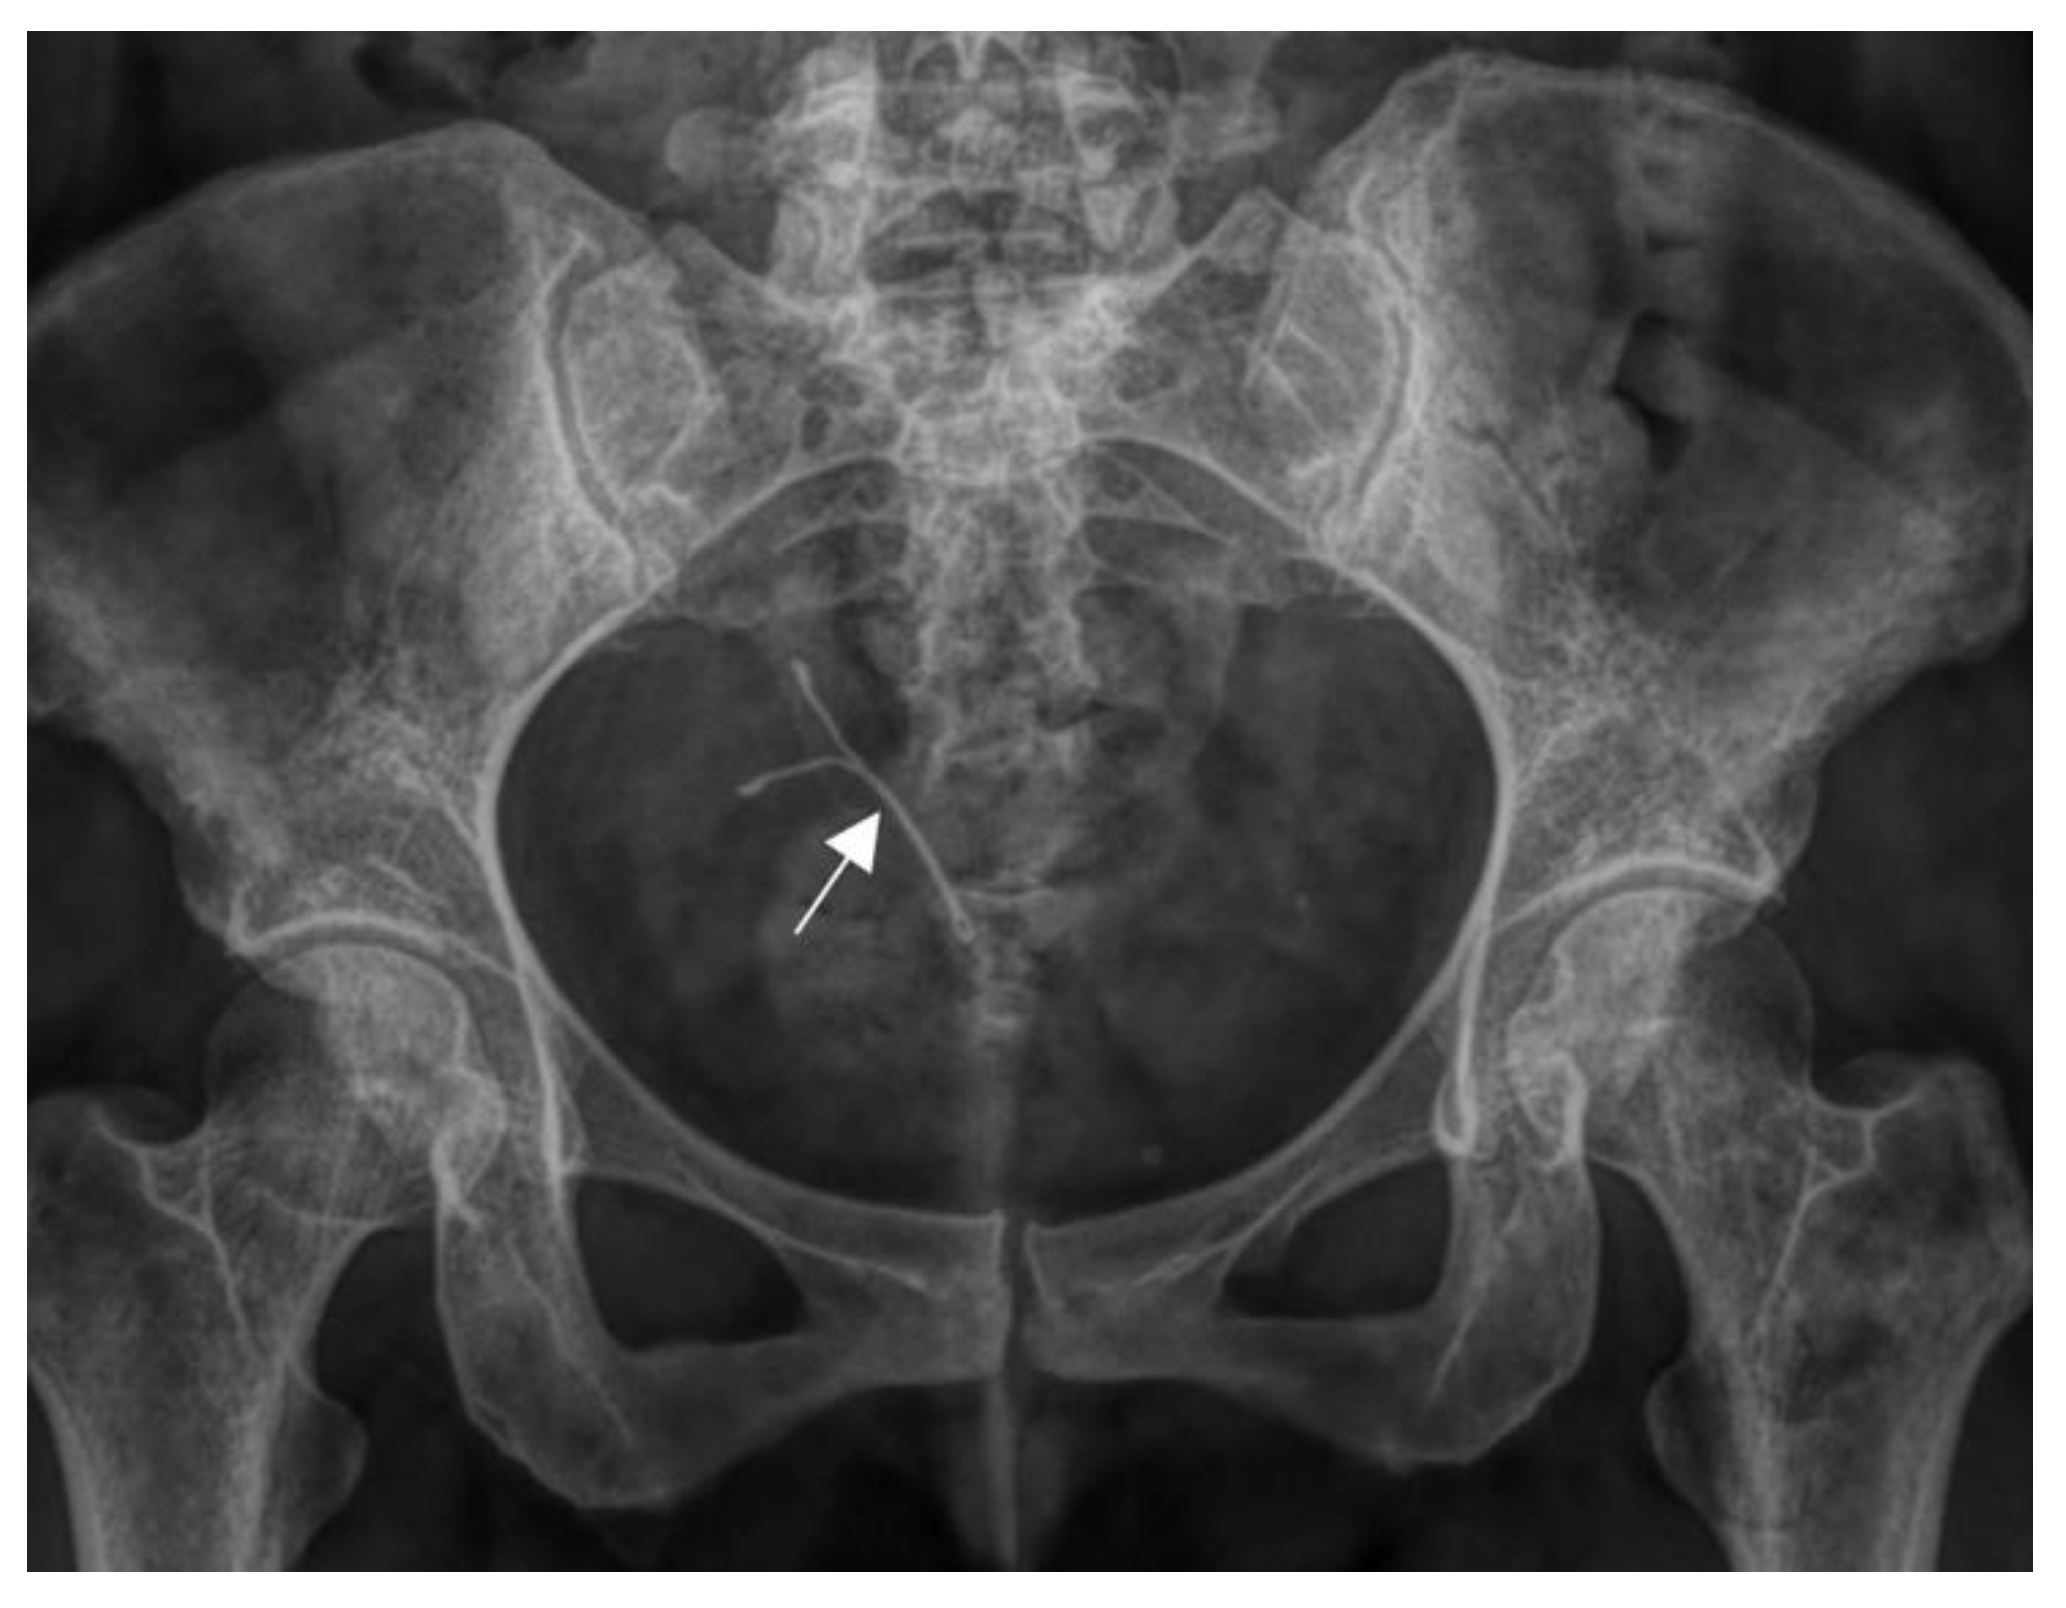

To complete the diagnosis, a hysterosalpingogram was ordered. Before the procedure, a gynecological examination with a vaginal speculum was performed, revealing a well-structured septum completely separating the two vaginal cavities. The follow-up x-ray revealed an IUD in the right endometrial cavity (Figure 3).

Figure 3. Follow-up pelvic radiograph. An IUD is shown in the right endometrial cavity.